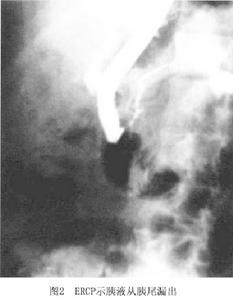

1.CT首先應通過CT檢查判斷是胰外瘺還是胰腺假性囊腫,觀察胰瘺周圍是否有膿腫形成和壞死組織存在大致了解假性囊腫的壁是否增厚。CT對判斷手術時機十分重要,並可揭示少見的胰內、外瘺如胰腺支氣管瘺和胰腺胸膜瘺,還可通過胰腺的薄層CT掃描和造影劑增強進一步了解胰腺的病變與胰管的走行與變化(圖1)。